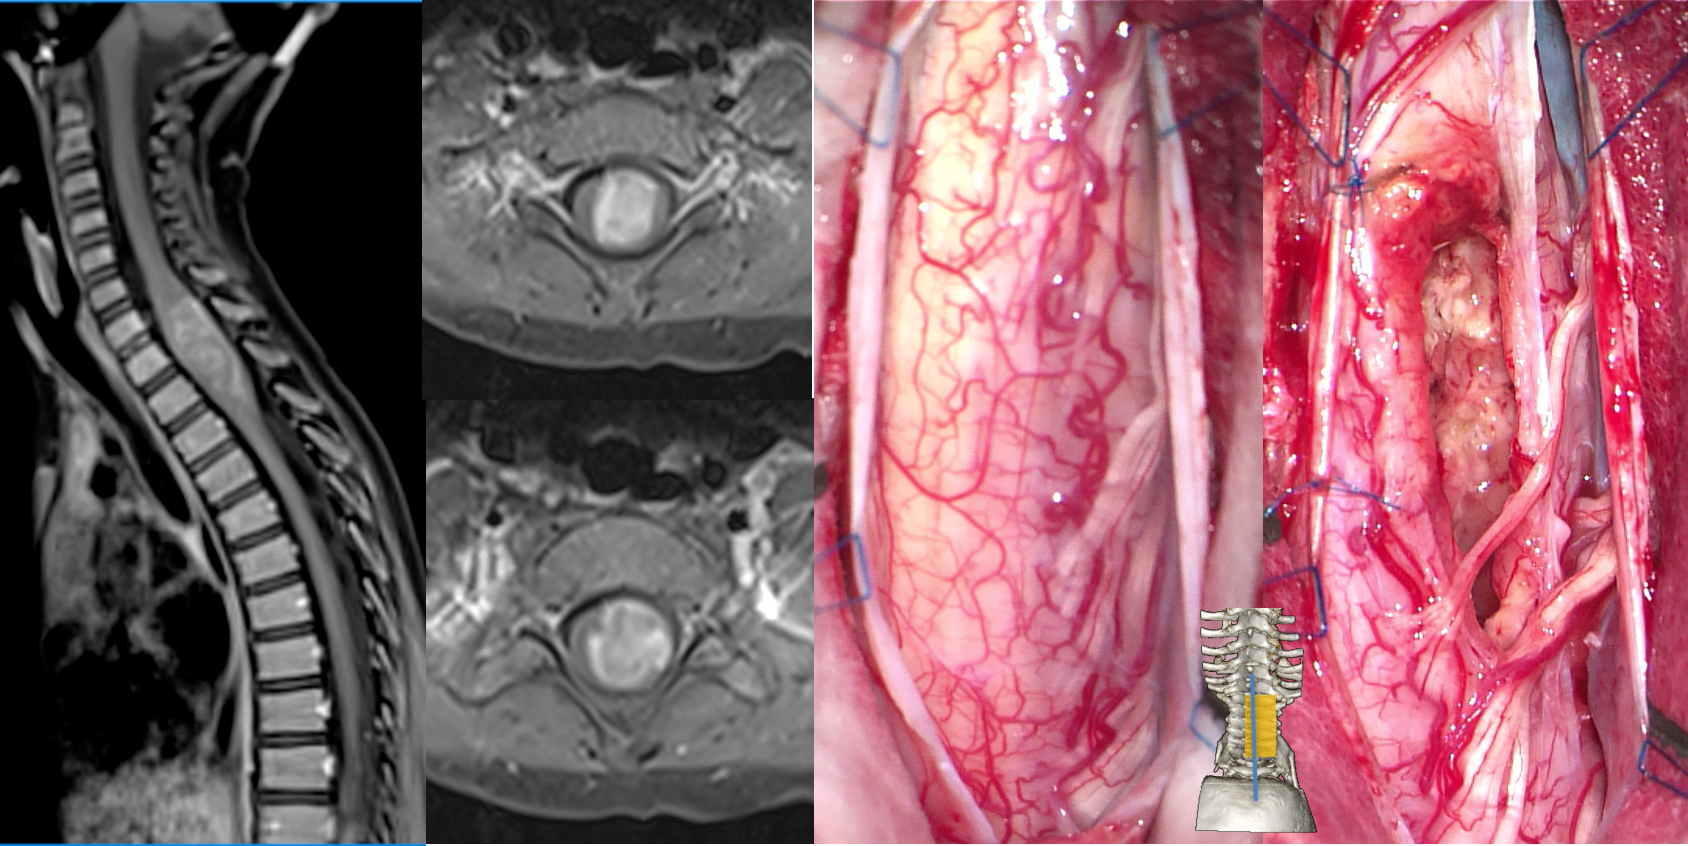

l’épendymome

pouvant être sporadique ou associé à la NF2, c’est une tumeur en règle générale centra-médullaire, extirpable par une ouverture du sillon médian postérieur (ci-dessous). l’épendymome intra-médullaire est en règle générale de grade 2, il est distinct de l’épendymome myxo-papillaire qui intéresse la queue de cheval, comme des épendymomes intra-crâniens qui ont une biologie différente.

les autres tumeurs gliales

on rencontre des astrocytomes diffus, des localisations spinales de gliomatose diffuse (ci-dessus gauche), des gliomes de haut grade (ci-dessus droite) ; la chirurgie a essentiellement un rôle de diagnostic hosto-pathologique et moléculaire, et de décompression (plastie ostéo-durale cf ci-dessus).